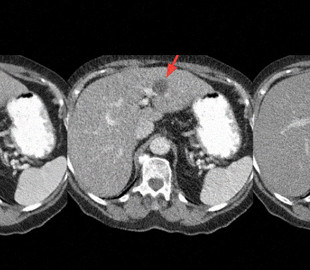

Изображения, полученные с помощью нового алгоритма (DL), итеративной реконструкции (IR) и при стандартной дозе излучения. Красными стрелочками отмечены повреждения печени, зеленым — уплотнение стенки легкого, а синим — эмфизема.